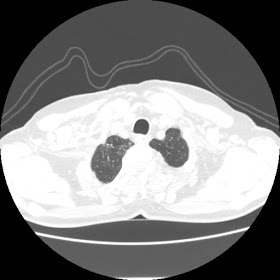

A 62 years old man with enlarged mole on chest since 2 months.

CT chest :-